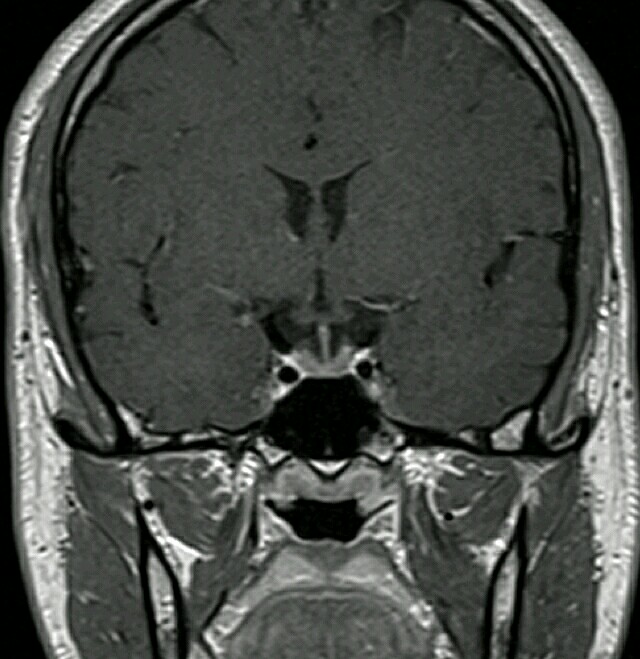

患者男性,28 岁,先天性嗅觉丧失,青春期延迟和不育。 图. 头颅 MRI:冠状位 T2WI(A、B)及 T1WI 对比增强(C) 图中示患者蛛网膜下池内、筛板上未见嗅球(图 A 箭头所示),同样未见嗅沟(图 B 箭头所示)。T1WI 对比增强可见脑垂体下前部,垂体柄未见异常。 诊断?